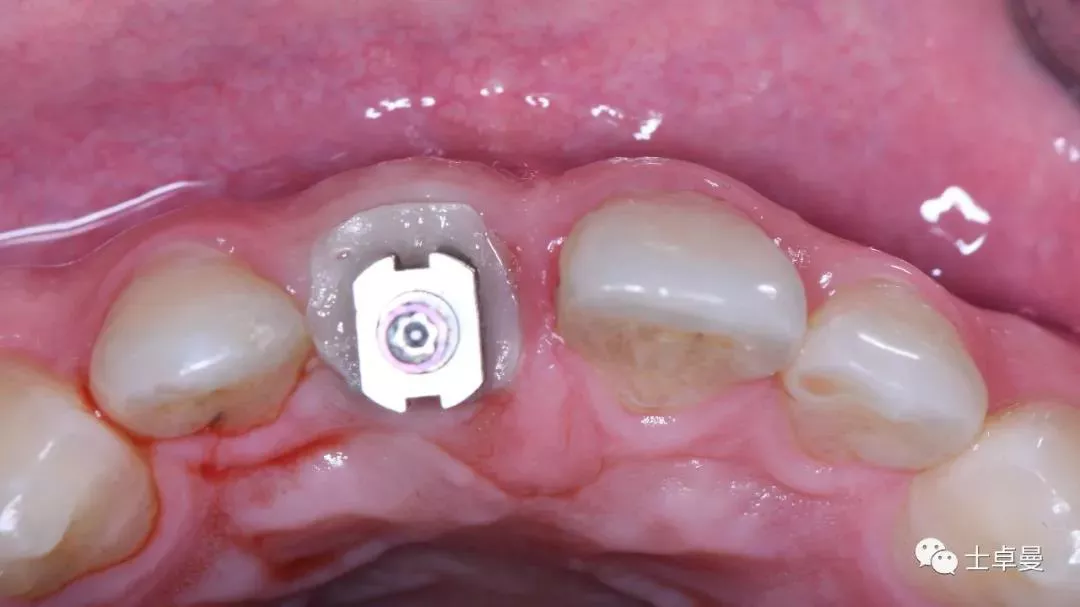

就位种植外科导板

指示杆观察备孔三维位置

种植体植入后,植体唇侧间隙内填塞骨粉0.25g,胶原骨100mg,安放愈合帽,明胶海绵暂时封闭创面

术后即刻CT示,种植体植入位置理想